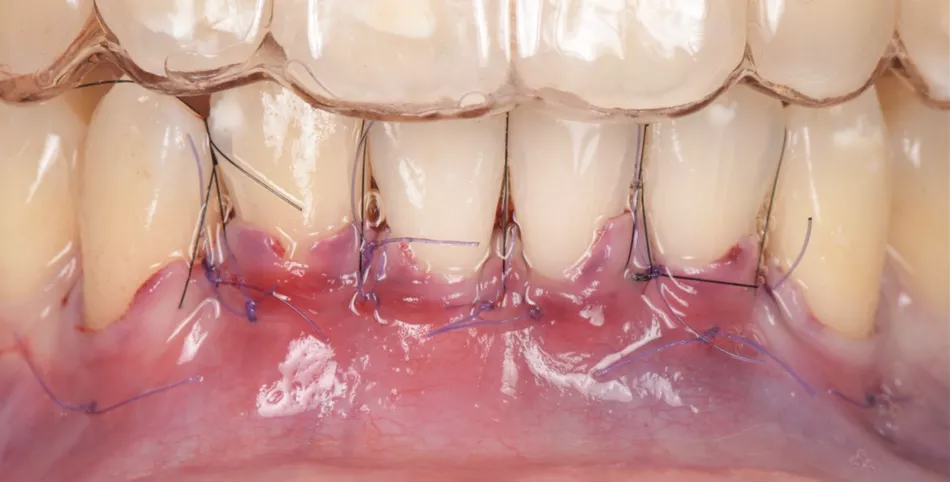

Two split-full-split flaps were raised from teeth #33 to #31 and #41 to #43, with beveled incisions at the base of the papilla (Fig. 3).

Fig. 3

De-epithelialization of the anatomical papilla (Fig. 4).

Fig. 4

Root planing and surface conditioning with Straumann® Prefgel® for 2 minutes (Fig. 5).

Fig. 5

The first connective tissue graft was placed on denuded roots of #43, #42, and #41 (Fig. 6), and the second on #31, #32 and #33 (Fig. 7), which all had previously been treated with Straumann® Emdogain®.

The buccal flaps were coronally displaced and sutured with 6/0 sutures and tension-free closure (Fig. 8).

Fig. 8